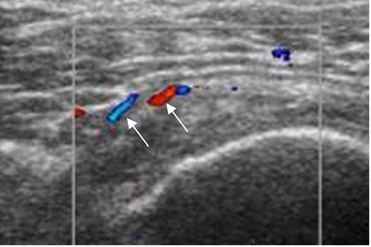

Fig 131. Tendinitis crónica del supraespinoso.

Ecografía doppler coronal. Neoformación vascular (Flechas), secundario a tendinitis crónica.